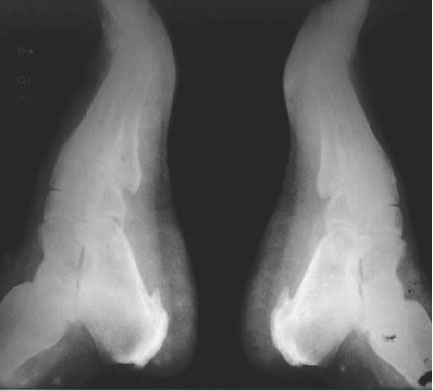

¿Y qué es el espolón calcáneo?

Es un crecimiento óseo sobre el hueso del talón, en especial en la parte inferior delantera del referido hueso, que se une con la fascia plantar: banda larga de tejido conectivo que se extiende desde el talón hasta la base de los dedos del pie, y cuando se estira excesivamente puede provocar ese crecimiento óseo o espolón.

La fascia plantar sostiene el arco longitudinal de la planta del pie y sirve para amortiguar los impactos durante las actividades de la vida diaria. El dolor se produce como consecuencia del esfuerzo y la inflamación de esta al tirar del hueso y comprimir una bolsa que rodea el espolón porque este demora mucho tiempo en formarse y puede pasar inadvertido por muchos años. Pero los microtraumas repetidos debido a deformidades como pies planos, exceso de arco, sobrepeso corporal, actividades físicas con calzados inadecuados y otras agresiones a los pies, son los desencadenantes de estos dolores. El espolón es un fenómeno secundario y no el origen del dolor.